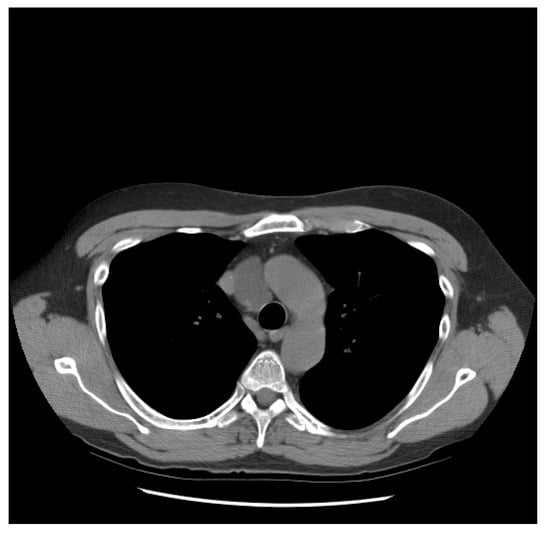

| Patient NSGCT Type | Status | Pathology of Primary | Stage at Time of Diagnosis | S-YSTemic Chemo | Date: Pathology after Chemo |

|---|---|---|---|---|---|

| 1 ETT | Cured | 100% S (elevated AFP) | IIX | BEP x1, VIP x3, paclitaxel (docetaxel), doxorubicin, gemcitabine, | 6/2012: 90% T, 10% ETT + adenocarcinoma |

| 2 S-YST | Cured | 5% E, 90% S, 5% Y | IIIC | BEP x4 | 5/2018, 4/2019, 4/2020: 99% S-YST + 1% T |

| 3 ETT | Cured | 80% ETT, 20% T | IIC | BEP x3 | 1/2018: T w/minute ETT |

| 4 S-YST | Died | NA Y in met | IIIC | BEP x4 | 9/2016: T 1/2021: S-YST |

| 5 ETT | Died | 100% E | IIIA | BEP x1, EP x3, TIP x4, POMB x2, ATP x4, TIP x1/HDC + SCT | 7/2019: Embryonal 11/2019: ETT 1/2020: Choriocarcinoma |

| 6. ETT | Died | 99% E, 1% T | IIIA | BEP x3, TIP x3, ATP | 9/2018: E, C 7/2019, 8/2019: 60% ETT + squamous cell carcinoma |

| 7 S-YST | Died | NA i(12p)+ in met | IIC | BEP x2, XELOX, ATP x2 | 8/2019: S-YST (Unresectable) |